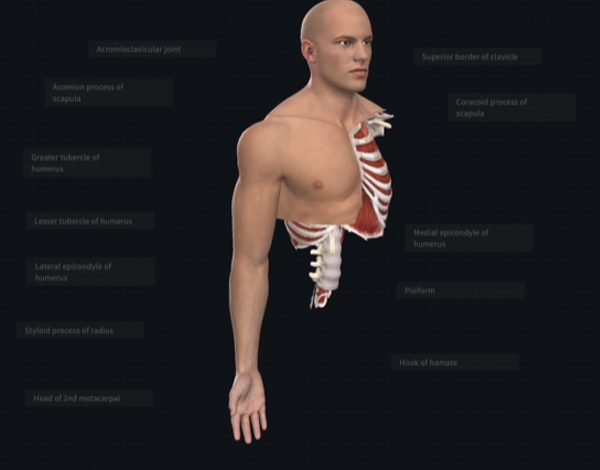

Get the benefit of using Anatomizz leading-edge technology to improve medical learning engagement and outcomes. Anatomizz which is built by doctors from reputed medical colleges elevates your medical teaching to a new level by giving your learners accurate anatomical content with an easy-to-use interface and interactive 3D graphics.

Using Anatomizz learners can dissect the virtual body layer by layer down to the skeleton with the touch of a finger without any hassle. It is a new-age medical teaching tool that ensures a very immersive medical learning experience seen like never before.

Cut body in sagittal, coronal, and transverse axis, zoom-in/zoom-out body parts, rotate organs, peel off parts layer-by-layer, pin, draw, take screenshots, split screen, and much more.